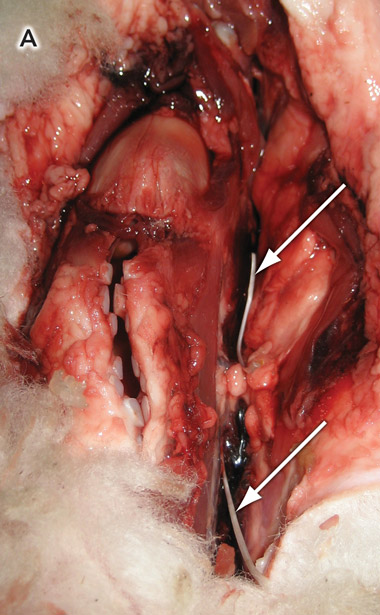

The specimen was prepared by removing excess wool and dissecting the laryngopharynx. The fishbones were placed in the paratracheal tissues and adjacent to the larynx (Box 2, A).

2 Placement of fishbones in the specimen